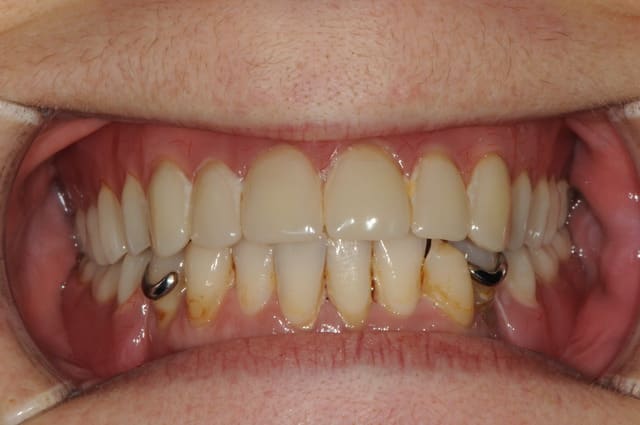

pour la petite histoire, la patient dépressive est venue il y a 4 ans pour la première fois.

ses dents étaient mobiles, elle était complexée, gardait souvent la mains devant la bouche quand elle parlait...

j'ai mis deux ans à la décider à sauter le pas et faire extraire ce qui lui restait en haut pour lui poser une PAC.

et encore 1 an et demi pour la décider à passer aux implants.

comme on peut le voir sur les premières photos, la forme des gencives était magnifique, si seulement j'avais pu poser des implants à ce moment là et profiter des papilles résiduelles que lui avait laissé son stellite...